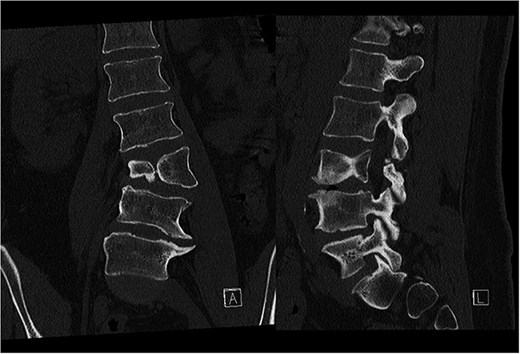

Preoperative CT demonstrating L3 hemivertebra; anteroposterior view (A) on the left side of the image, and lateral view (L) on the right side of the image.

CT-based 3D reconstruction revealed a semi-segmented hemivertebra at L3, resulting in a 32° Cobb angle of congenital scoliosis (Fig. 4). We decided to perform hemivertebra resection, L3 laminectomy, L2-L4 fixation with L3–4 cage fusion, and scoliosis correction. CT-based resection was 3D planned using EBS software (Fig. 6). Fixation from L2 to L4 was achieved using pedicle screws under fluoroscopic guidance, followed by L3 laminectomy. After accessing the L3–L4 disc space, a 3D real-time EMN-guided total resection of the L3 hemivertebra was performed (Fig. 6), and a cage with autogenous bone graft was inserted at the L3–L4 level. The left-sided L3 nerve was found to have an accessory branch, which was successfully preserved. Scoliosis was corrected using standard deformity correction maneuvers.